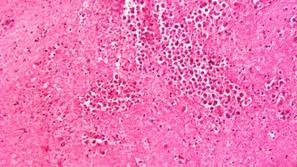

Ameba

Smrtonosno

Možganojeda ameba v vodovodu

Zdravstvene oblasti v Louisiani so v vodovodnem sistemu, ki oskrbuje več kot 12.000 ljudi, odkrile prisotnost izjemno n…